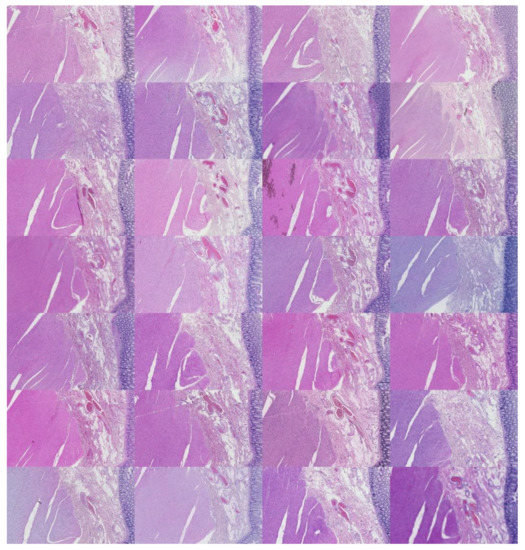

The preprocessing stage began with 66 WSI scans; we digitally cropped one region of interest (ROI) of size 1440 × 904 pixels for each tissue type in each slide. This resulted in three sets of images of 66 ROIs each, one set for the kidney, one for the skin, and one for the colon tissue. Cropping was used to minimize the presence of the non-tissue-related background, such as dust, hair, fibers, and other artifacts from previous preprocessing steps. The selected region coordinates were approximately the same within each tissue type. Each ROI was localized to cover an approximately sufficient area in each tissue type. Figure 3 shows samples of such ROIs for each tissue type amongst nine randomly chosen laboratories (three laboratories per tissue type).

Figure 3.

For illustration purposes, three ROIs from three laboratories per tissue type (column-wise). The first column is skin, the second column is kidney, and the last column is colon.

We cropped the original ROIs into 128 image tiles per ROI to conduct supervised learning. The image patches were non-overlapping and 113 × 90 pixels each in size. Consequently, this amounted to 8488 image patches distributed equally amongst 66 laboratories per tissue type. There were 25,462 tiles in total across all laboratories. The ground truth of each patch was the laboratory from which the original ROI was processed. This resulted in 66 ground truth classes, one for each laboratory containing 128 image patches. Examples are shown in Figure 7.

Figure 7.

For illustration purposes, three tiled ROIs from three laboratories (per row). The first row is kidney, the second is skin, and the last is colon.